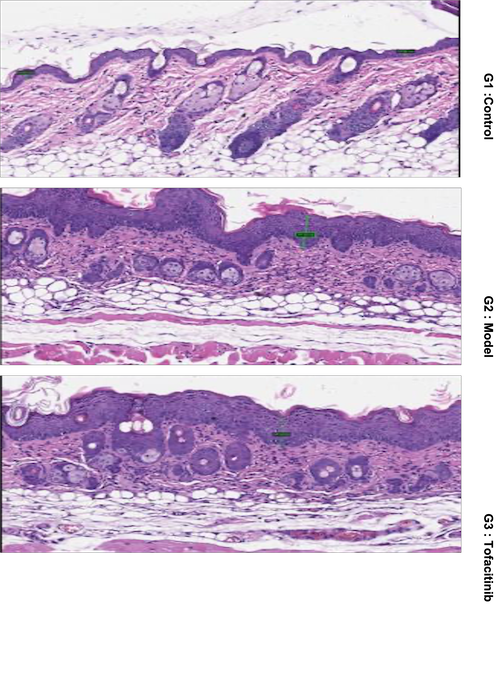

Imiquimod (IMQ)-Induced Psoriasis in Mice

Animal: BALB/c mice, female, 7.5 weeks

Modeling: IMQ painted on shaved back skin daily

Reference Drug: Tofacitinib, p.o., BID

Readouts: Body weight, PASI score, skin thickness, pathology